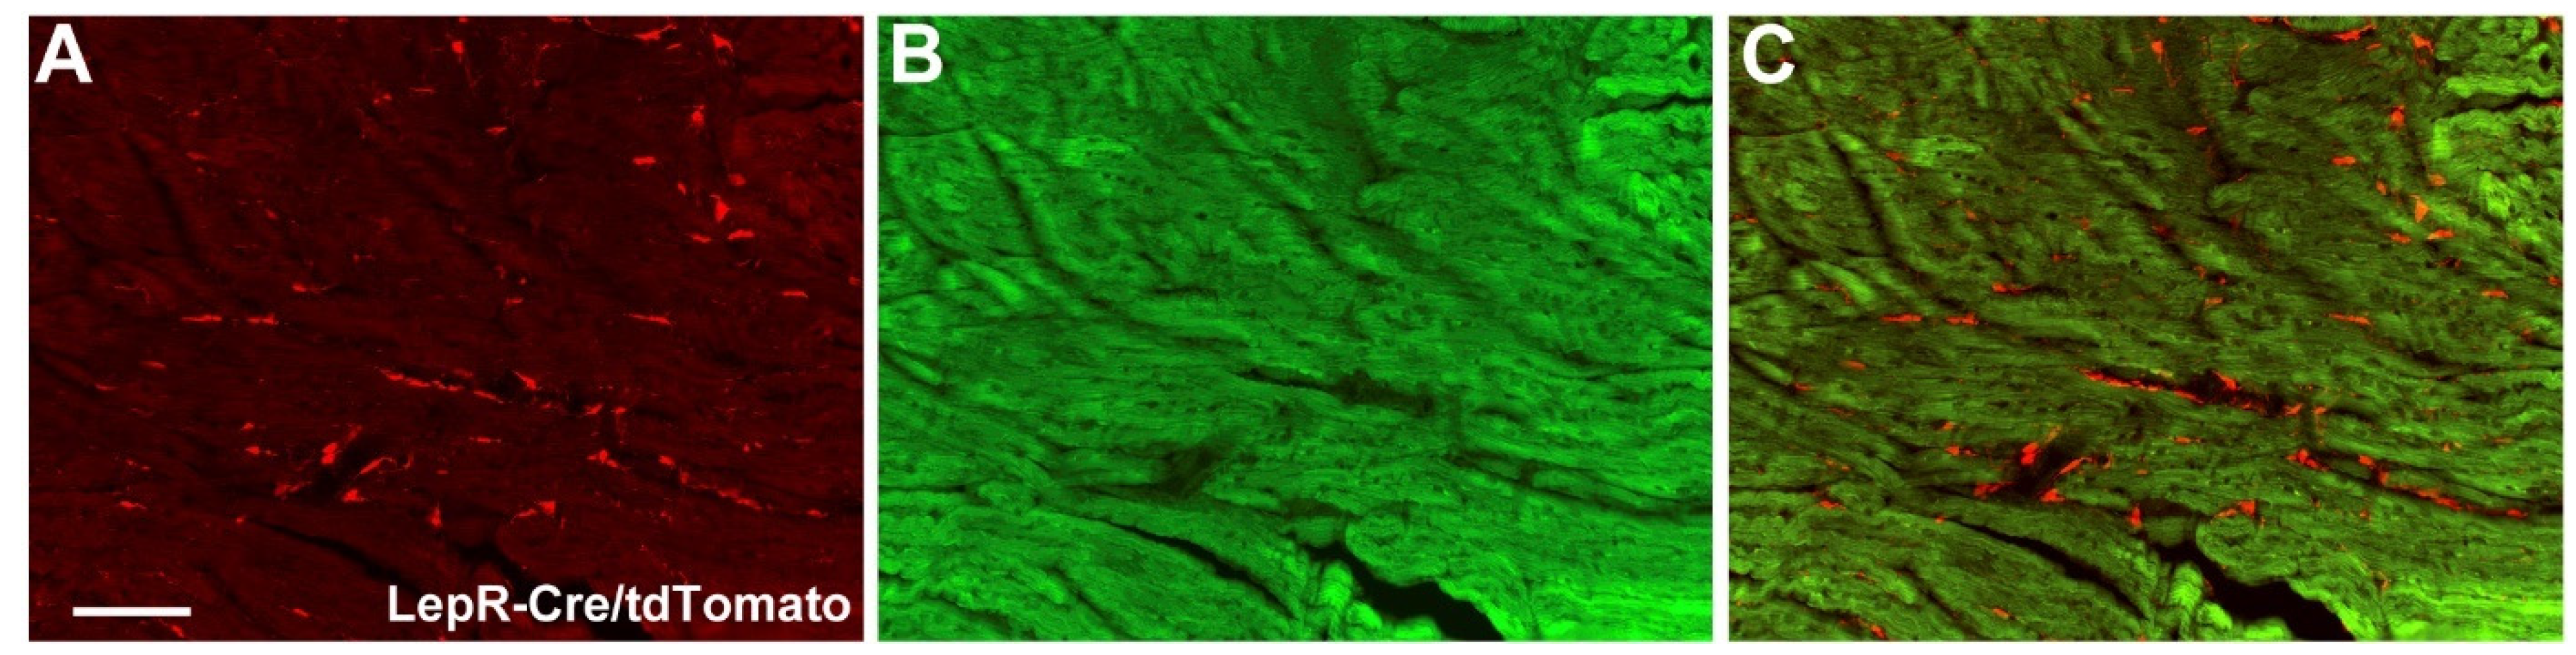

4.1. Animals